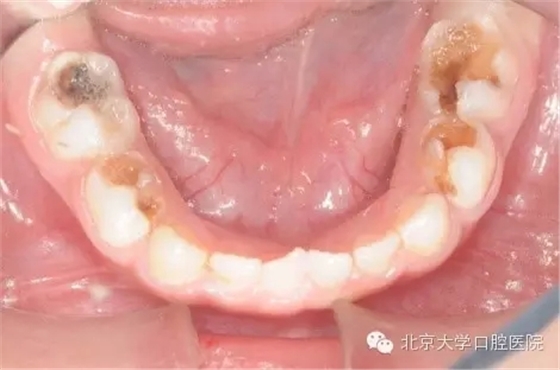

全麻治療因?qū)⒂?jì)劃進(jìn)行的所有治療集中在一次完成,而這些治療在常規(guī)門診時(shí)可能要十余次才能完成,因此牙齒治療的反應(yīng)有疊加,在全麻治療術(shù)后可能出現(xiàn)明顯的咬合不適,牙齒腫痛等情況,請(qǐng)遵醫(yī)囑進(jìn)行有針對(duì)性的處理,一般說來一段時(shí)間后這些癥狀都能消退。7為什么孩子的牙做了牙套?

全麻治療中醫(yī)生對(duì)缺損較大的后牙經(jīng)常會(huì)采用“預(yù)成冠”修復(fù)的方法,預(yù)成冠由不銹鋼制成,可以很好的恢復(fù)牙齒的外形并預(yù)防牙齒及充填體折斷,并不影響牙齒替換。